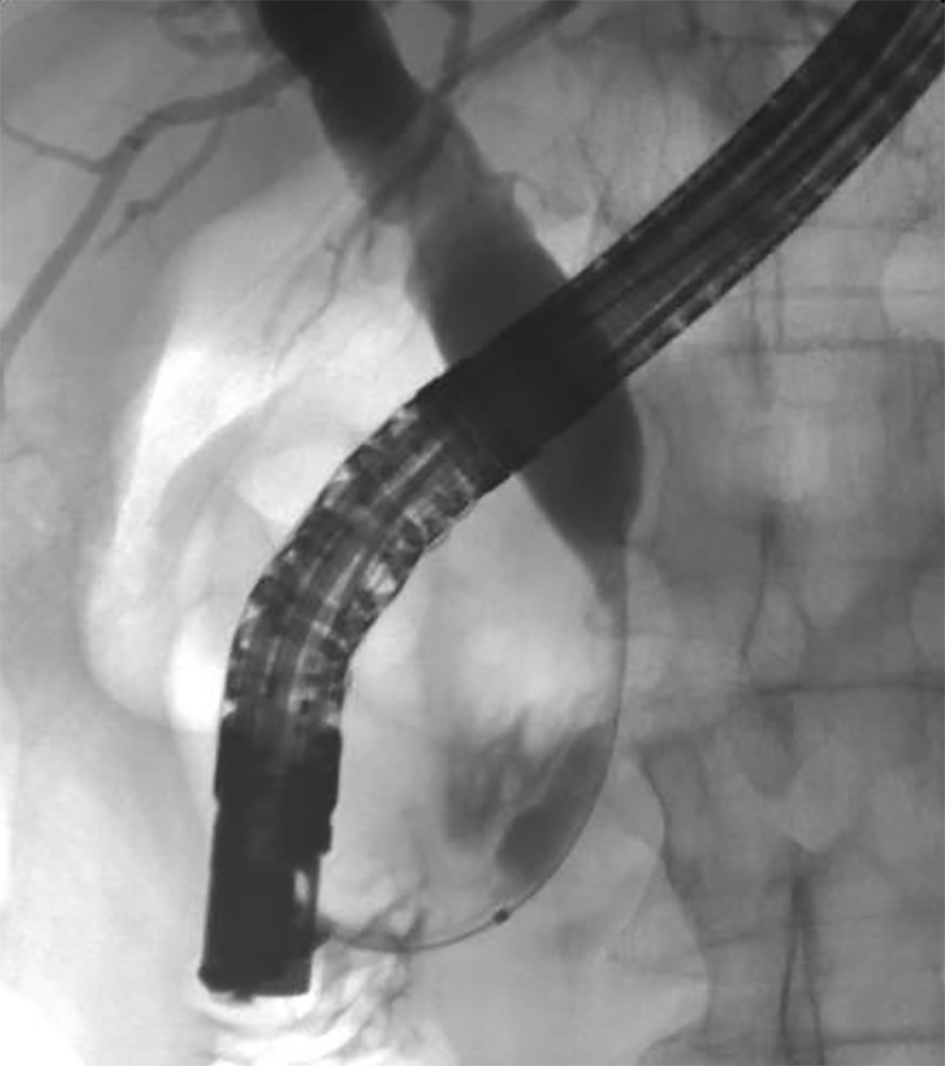

A review of his medical records showed that he had presented to a community medical center 8 years prior with a 5-month history of gastroesophageal reflux, acholic stools, jaundice, dark urine and a total bilirubin of 6.0 mg/dL (reference range 0.2 - 1.4 mg/dL). His initial CT scan demonstrated a 4.6 cm mass in the head of the pancreas (Fig. 2). He was subsequently referred to our tertiary-care university medical center, where an ERCP and brushings demonstrated pancreatic ductal irregularities noted to be “suspicious for malignancy”, although pathological analysis was inconclusive (Fig. 3). His peak CA19-9 was 129 U/mL (reference range 0 - 37 U/mL) and his CEA was 1.7 ng/mL (reference range 0 - 5 ng/mL). An upper endoscopy with ultrasonography and fine-needle aspiration (FNA) was completed, demonstrating a 30 × 20 mm mass in the head of the pancreas with irregular borders, which obstructed the common bile duct and appeared to invade the portal vein. The endo-ultrasonographic appearance was consistent with adenocarcinoma, and he was staged as T3N0Mx. FNA specimens were independently reviewed by three cytopathologists from two institutions and were consistently read as well-differentiated mucinous adenocarcinoma (Fig. 4). The patient was otherwise in excellent health and deemed to be a good candidate for pancreaticoduodenectomy. On surgical exploration, the mass was found to be unresectable and the patient was upstaged to stage III, T4N0Mx. The operative report describes tumor completely encircling the superior mesenteric vessels, portal vein involvement and induration of the pancreas from head to tail. The surgical team aborted the planned pancreaticoduodenectomy and opted to perform a palliative cholecystectomy and choledochojejunostomy.

![]() Click for large image | Figure 3. ERCP image of mass effect on the common bile duct. |